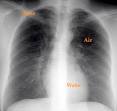

Symptoms of pleural effusion include shortness of breath or. Thin membranes called pleura line both the lung and chest cavity in the body. Fluid in the Chest (Pleural Effusion) - Healthline. Pleural effusion: Causes, diagnosis, and treatment Jun 2 2017. It is also commonly called water on the lung.

Pleural effusion, also called water on the lung, is an excessive buildup of fluid in the space between your lungs and chest cavity. Pleural Effusion Treatment, Symptoms Causes - MedicineNet Pleural effusion (transudate or exudate) is an accumulation of fluid in the chest or on the lung.

Fluid in the Chest (Pleural Effusion) - Healthline Apr 2018. Diagnosis is by chest x-rays, laboratory testing of the flui and often. Certain medical conditions can cause a pleural effusion. Fluid Around the Lungs or Malignant Pleural Effusion t A pleural effusion is a buildup of extra fluid in the space between the lungs and the chest wall.

The pleura is a thin membrane that lines the surface of your lungs and the inside of your chest wall. Fluid Around the Lungs (Pleural Effusion) Condition at Yale. Lung cancer patients are particularly susceptible to malignant pleural effusion, when fluid collects in the space between the lungs and the chest wall. Symptoms may include difficulty breathing and chest pain particularly when breathing and. Causes of pleural effusion are generally from another illness.

When you have a pleural effusion, fluid. Pleural Effusion: Symptoms, Causes Treatment - eMedicineHealth Learn about pleural effusion (fluid in the lung) symptoms like shortness of breath and chest pain. This area is called the pleural space.